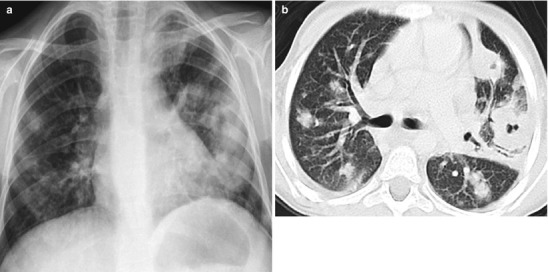

Fig. 13.28.

Staphylococcal abscess. A 9-year-old boy with chronic granulomatous disease with persistent fever had a chest x-ray (a) showing multiple rounded opacities in both lung fields. Axial CT scan (b) demonstrates multiple pulmonary nodules, some on the left has cavitation. These are proven to be multiple abscesses

Bone marrow transplant requires complete eradication of the immune system. Early infectious complications are frequently caused by bacteria and fungi, most commonly Gram-negative bacteria (Pseudomonas and Klebsiella) and Aspergillus (Fig. 13.29). Widespread use of long-term indwelling catheters has led to an increased incidence of both staphylococcal and streptococcal pneumonia. Chest radiographs may show classic focal or lobar consolidation although atypical appearance can also be seen. Children are also at increased risk of viral infections, most importantly RSV, Herpes simplex, Adenovirus, and Varicella. Immunosuppressive therapy following solid organ transplantation predisposes a patient to recurrent pulmonary infections. In these patients, viral infections can be life-threatening, but Pneumocystis and fungal infections (Aspergillus and Candida) can also be seen (Collingsworth 2005).

Fig. 13.29.

Aspergillosis in the immunocompromised. Chest radiograph of a 3-year-old boy status post bone marrow transplant for leukemia (a) showing diffuse interstitial and alveolar disease with suspected cavity in the right upper lobe (arrow). Axial CT image (b) confirms the “air-crescent sign” of aspergillosis and the diffuse interstitial/alveolar disease